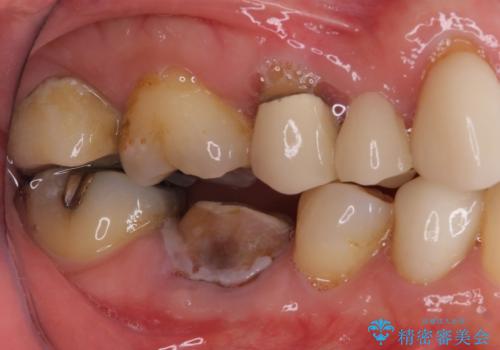

- 他院で矯正治療を終えたものの、むし歯や欠損部の治療が進められないとのことで来院された患者様です。

欠損部や、銀歯やむし歯の大きな歯はセラミッククラウンやブリッジに、小さいむし歯はセラミックインレーにて治療を行うこととしました。